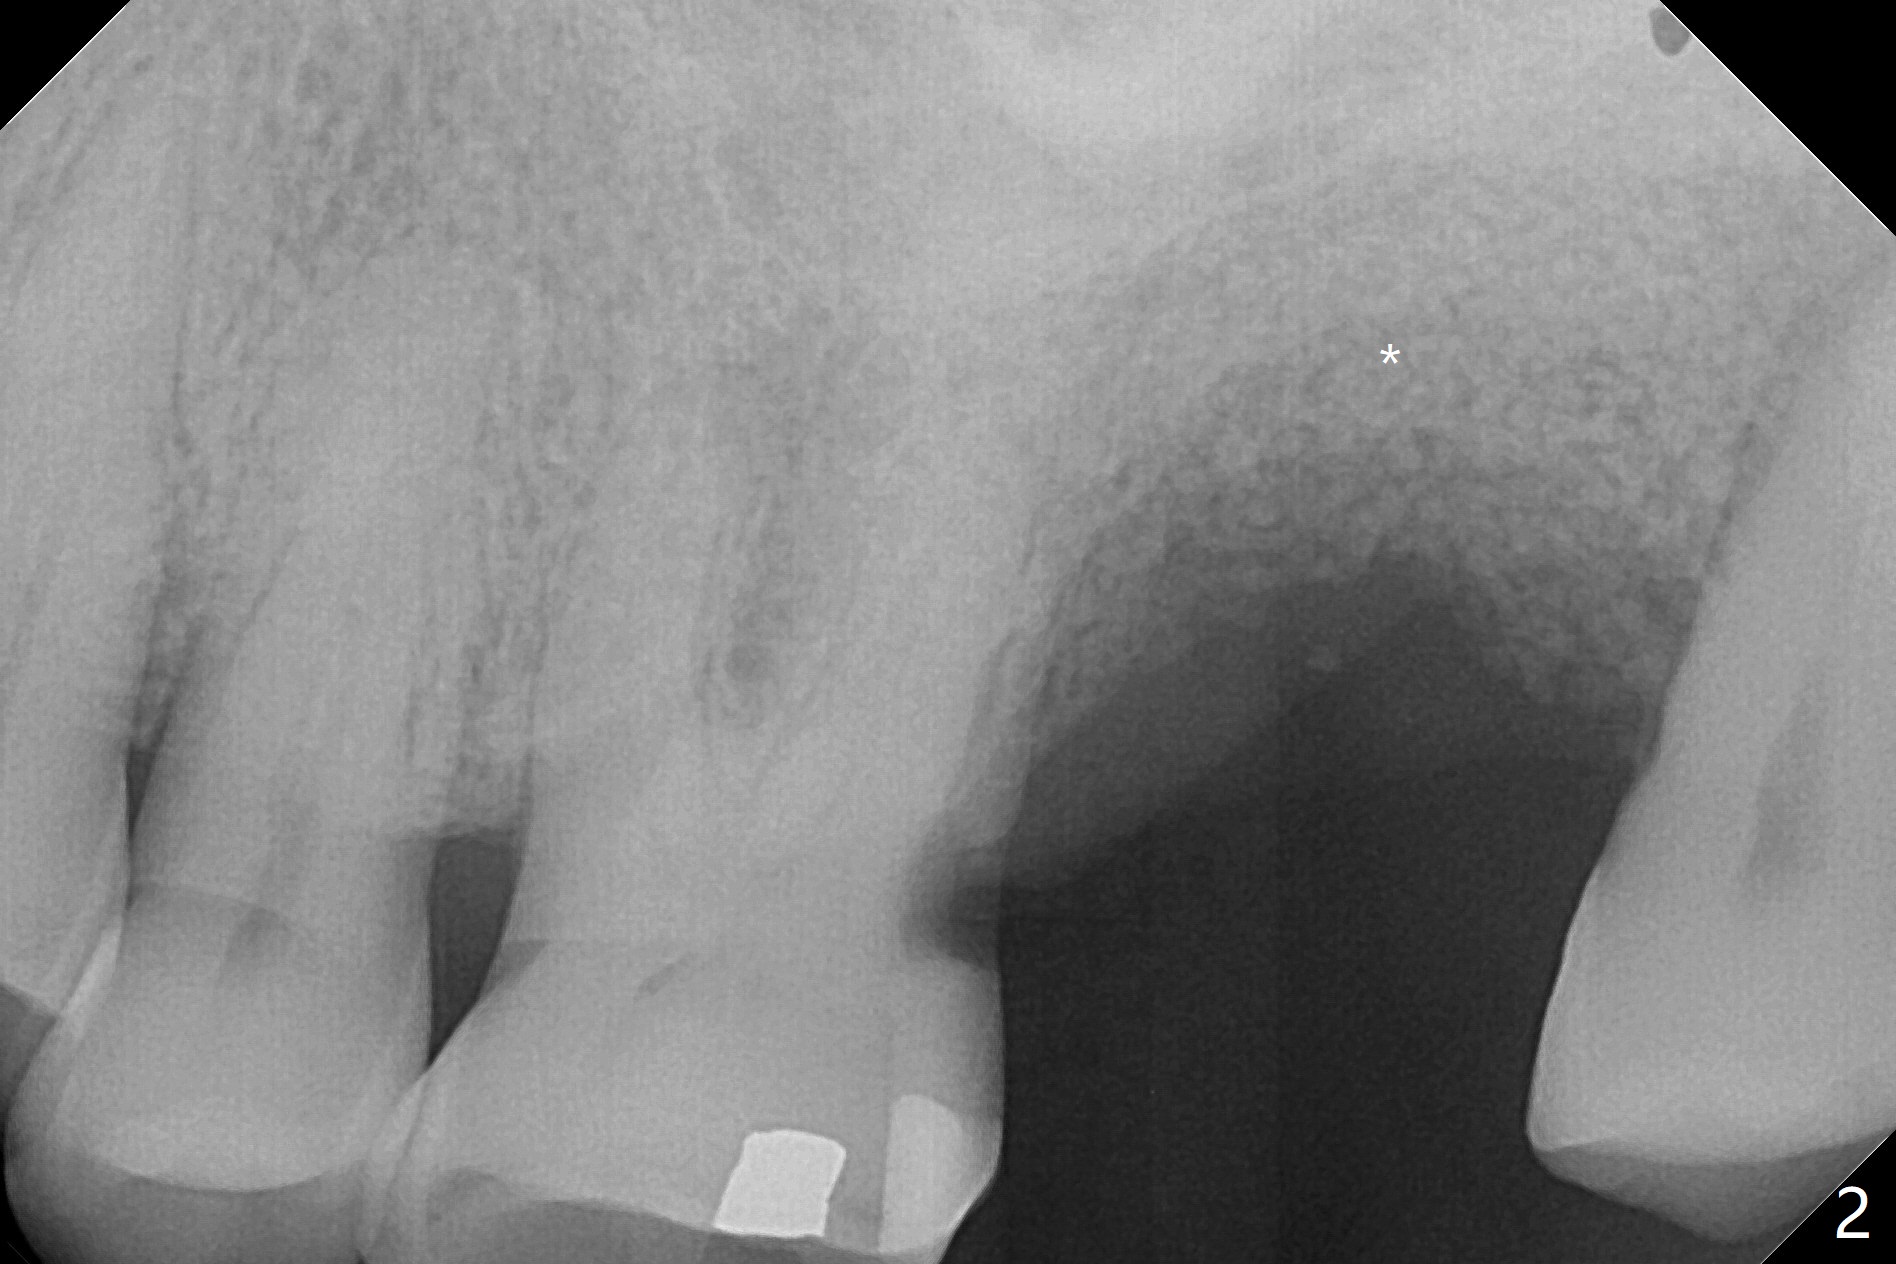

A 60-year-old woman has had an immediate implant placed at #15 with endo-perio disease. The crown dislodges with abutment and implant mobility <4 years post cementation (Fig.1). There is loss of the distopalatal walls post implant removal. Sticky bone is placed post debridement (Fig.2: *). After PRF and (difficult) PGA suturing, acrylic dressing is applied.